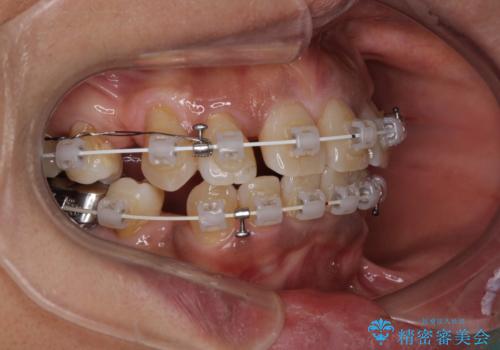

- 審美装置

- 2年4ヶ月

- 八重歯やクロスバイトを気にして来院された患者様です。

口元の突出感はありませんでしたが、デコボコが強く、非抜歯矯正とすると出っ歯仕上がりとなる可能性があったため、上下左右の第一小臼歯4本を抜歯し、ワイヤー装置にて矯正治療を行うこととしました。